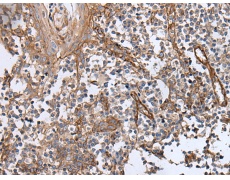

IHC positive control: |

Human tonsil and human colorectal cancer |

40-200 |